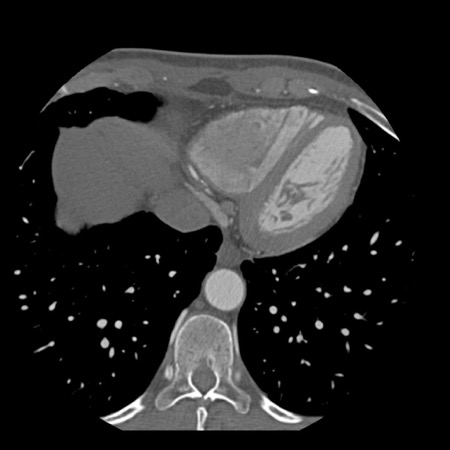

case 1 – CAD-RADS 2/P1

First, scroll through the scan.

Not all images are included. Some images without any abnormalities are skipped

from the series.

How would you describe the findings on the coronary CTA?

The findings are:

- Agatston score of

this patient was 14 (P1). Please, also note the calcification of the aortic valve. - Some partially

calcified and calcified plaques are present in the LAD with mild stenosis

(25-49%). - Calcified-plaque in

the LCX causing minimal stenosis (<25%). - Non-calcified

plaque in the distal RCA causing minimal stenosis (<25%). - This patient classifies

as CAD-RADS 2/P1, which means no further workup is needed.